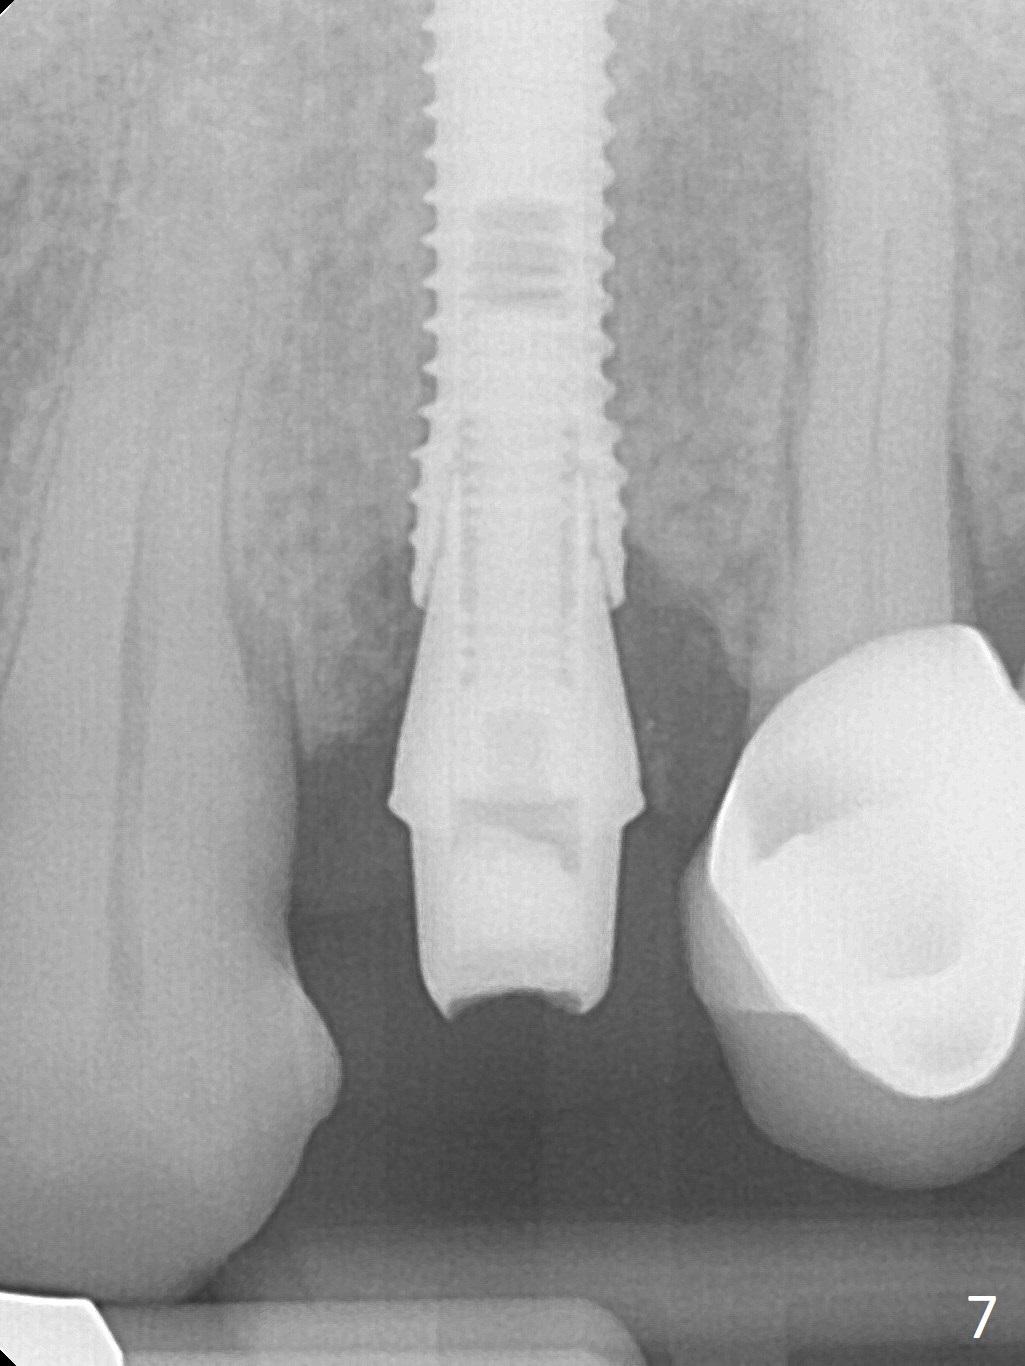

After extraction of the oval-shaped residual roots at #12 (Fig.1), osteotomy is initiated in the palatal socket for 18 mm; since the root of the canine curves distal (Fig.2 red dashed line), the osteotomy cannot afford to move mesial and extend more apical. A 3.8x15 mm implant is placed with > 50 Ncm (Fig.3). With immediate placement of a 4.5x4(3) mm abutment, an immediate provisional is fabricated to close the sockets (Fig.4 P). The provisional has clearance from the RPD clasps (Fig.5). In fact the implant could be longer, as shown by immediately postop panoramic X-ray (Fig.6). The implant seems to be osteointegrated 3 months postop (Fig.7). The tooth #13 is symptomatic with caries (Fig.8 C) 7 months post #12 crown cementation; the #13-15 FPD dislodges. The upper left quadrant is cold and hot sensitive 2.5 months post RCT (Fig.9); although there is mild percussion at #13, pulpal test shows that the tooth #15 has lingering pain. The FPD was recemented temporarily after RCT; it cannot be removed. The implant crown has been loose for several months during the pandemic before he returns 2 years 7 months post cementation. In fact the abutment has been not seated completely (from Fig.3 to 9). The crown/abutment is removed from the mouth; the crown is sectioned and separated from the abutment; the latter is reseated, but incompletely (Fig.10 <). With suspicion of the mesial crestal contact, profile drills 4.6 and 5.5 mm are used without effect. A new (old probably being worn) and longer (easy to turn in the narrow space) abutment is finally seated completely (Fig.11 (no gap)). After occlusal adjustment, abutment level impression is taken for a new crown.